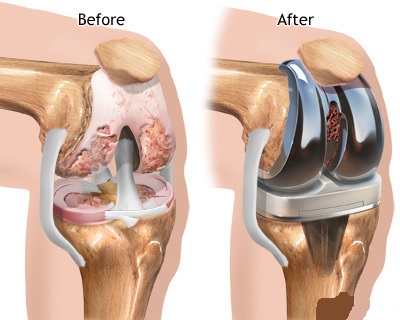

Medications, walking supports and altering activity levels may no longer be helpful after the knee disease progresses beyond a certain level. If you are at this stage, Total Knee Replacement (TKR) surgery is the best treatment option, as it corrects leg deformity, relieves pain and allows you to easily perform your daily activities.

In knee replacement we perform :